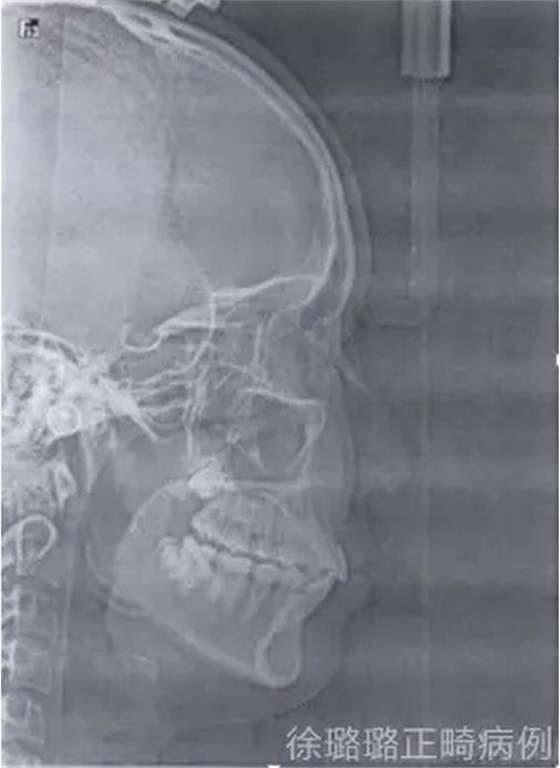

影像學(xué)檢查

X 線檢查:替牙列,上頜雙側(cè)尖牙埋伏阻生(含牙囊腫),四顆第三恒磨牙牙胚存在。

前牙 CT 檢查:上頜雙側(cè)尖牙埋伏阻生——雙側(cè)尖牙的牙冠均在側(cè)切牙根方的唇向位。